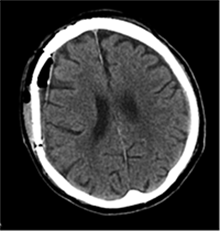

53 m. vyras sumuštas gatvėje ir greitosios medicinos pagalbos atvežtas į Priėmimo skyrių. Pacientui atlikta galvos kompiuterinė tomografija (GKT). Rasta: poūmė, stora, apie 16 mm dydžio subdurinė hematoma (SDH) dešinėje pusėje konveksitaliai ir ūmi nedidelė SDH kairėje pusėje frontoparietaliai. Vidurio struktūrų dislokacija (VSD) į kairę – minimali. Kairėje – kaukolės skliauto linijinis lūžis. Nustatyta nosies kaulų, nosies pertvaros, dešiniojo viršutinio žandikaulio kaktinės ataugos ir kūno, sinuso sienelių lūžių, dešinės akiduobės medialinio krašto lūžių ir dešiniojo skruostinio lanko lūžių (1 pav.). 2020 m. liepos mėn. pacientas skubos tvarka operuotas: atlikta dešinė kraniotomija, pašalinta hematoma. Atlikus kontrolinę GKT, buvo matyti, kad pašalinta didžioji hematomos dalis (2 pav.). Pacientas konsultuotas veido ir žandikaulio chirurgo, skubus chirurginis gydymas neindikuotas. Praėjus 3 savaitėms, pacientas, esant gerai funkcinei ir neurologinei būklei, tolesnio gydymo perkeltas į slaugos ligoninę, vėliau išleistas gydytis ambulatoriškai.

1 pav. Prieš pirmąją operaciją (poūmė, stambi, iki 16 mm SDH apie dešinįjį pusrutulį, ūmi nedidelė SDH kairėje F-P; VSD į kairę ~3 mm)

2 pav. Po pirmosios operacijos (didžioji hematomos dalis pašalinta, VSD be dislokacijos)